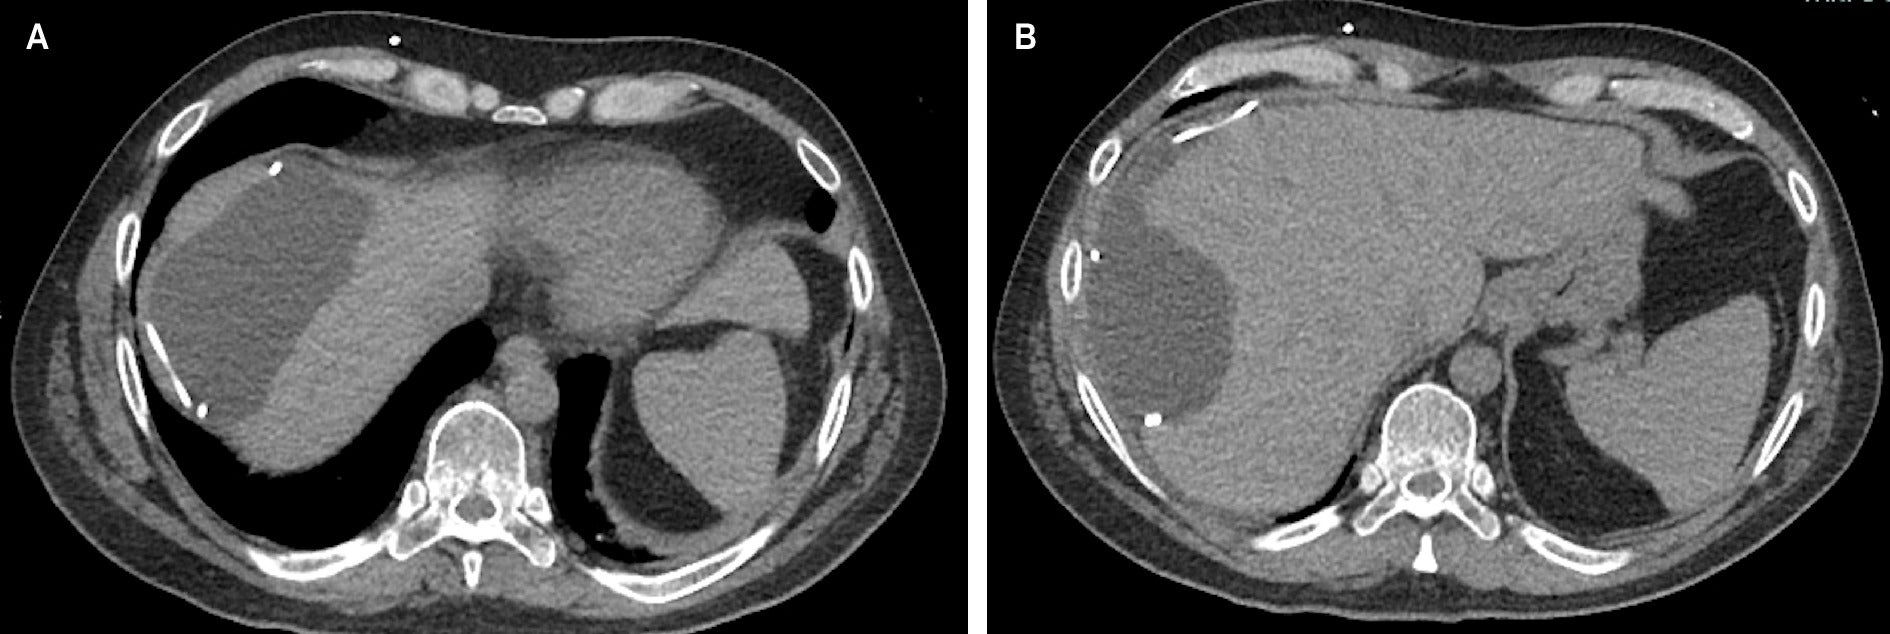

An axial CT without contrast reveals the presence of a large fluid-density mass in the right upper quadrant measuring 10.9 × 11.5 × 5.6 cm. This demonstrates a mass effect on the liver, with deformity of the hepatic contour. The VP shunt catheter can be seen as the dense curvilinear structure within the collection ( Figure 1 ).

(A, B) Axial CT without contrast shows a large mass in the right upper quadrant measuring 10.9 × 11.5 × 5.6 cm, appearing as a loculated collection that deforms the contour of the liver containing the distal tip of a VP shunt catheter.